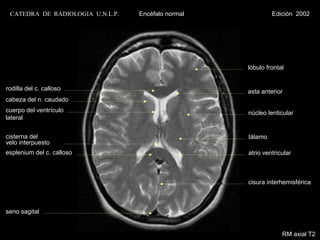

CATEDRA DE RADIOLOGIA U.N.L.P.   Encéfalo normal                Edición 2002

lóbulo frontal

rodilla del c. calloso                                 asta anterior

cabeza del n. caudado

cuerpo del ventrículo                                   núcleo lenticular

lateral

cisterna del                                            tálamo

velo interpuesto

esplenium del c. calloso

cisura interhemisférica

seno sagital

RM axial Densidad Protónica